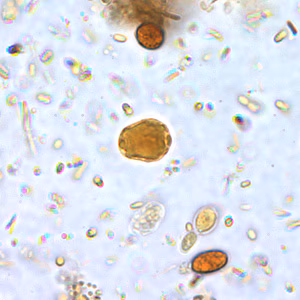

A 29-year-old man went to a local health clinic with complaints of intermittent diarrhea for a few months. He did not report any other symptoms but said he had difficulty sleeping sometimes. A stool specimen was collected and preserved in both 10% formalin and polyvinyl-alcohol (PVA). An ova and parasite (O & P) examination was performed. Figure A shows what was seen on a concentrated wet mount preparation, and Figure B shows what was seen on a wet mount stained with iodine. Figures C and D show what was seen on a trichrome stained smear made from the PVA preserved specimen. Objects measured 7 to 10 µm in diameter. What is your diagnosis? Based on what criteria?

Figure B